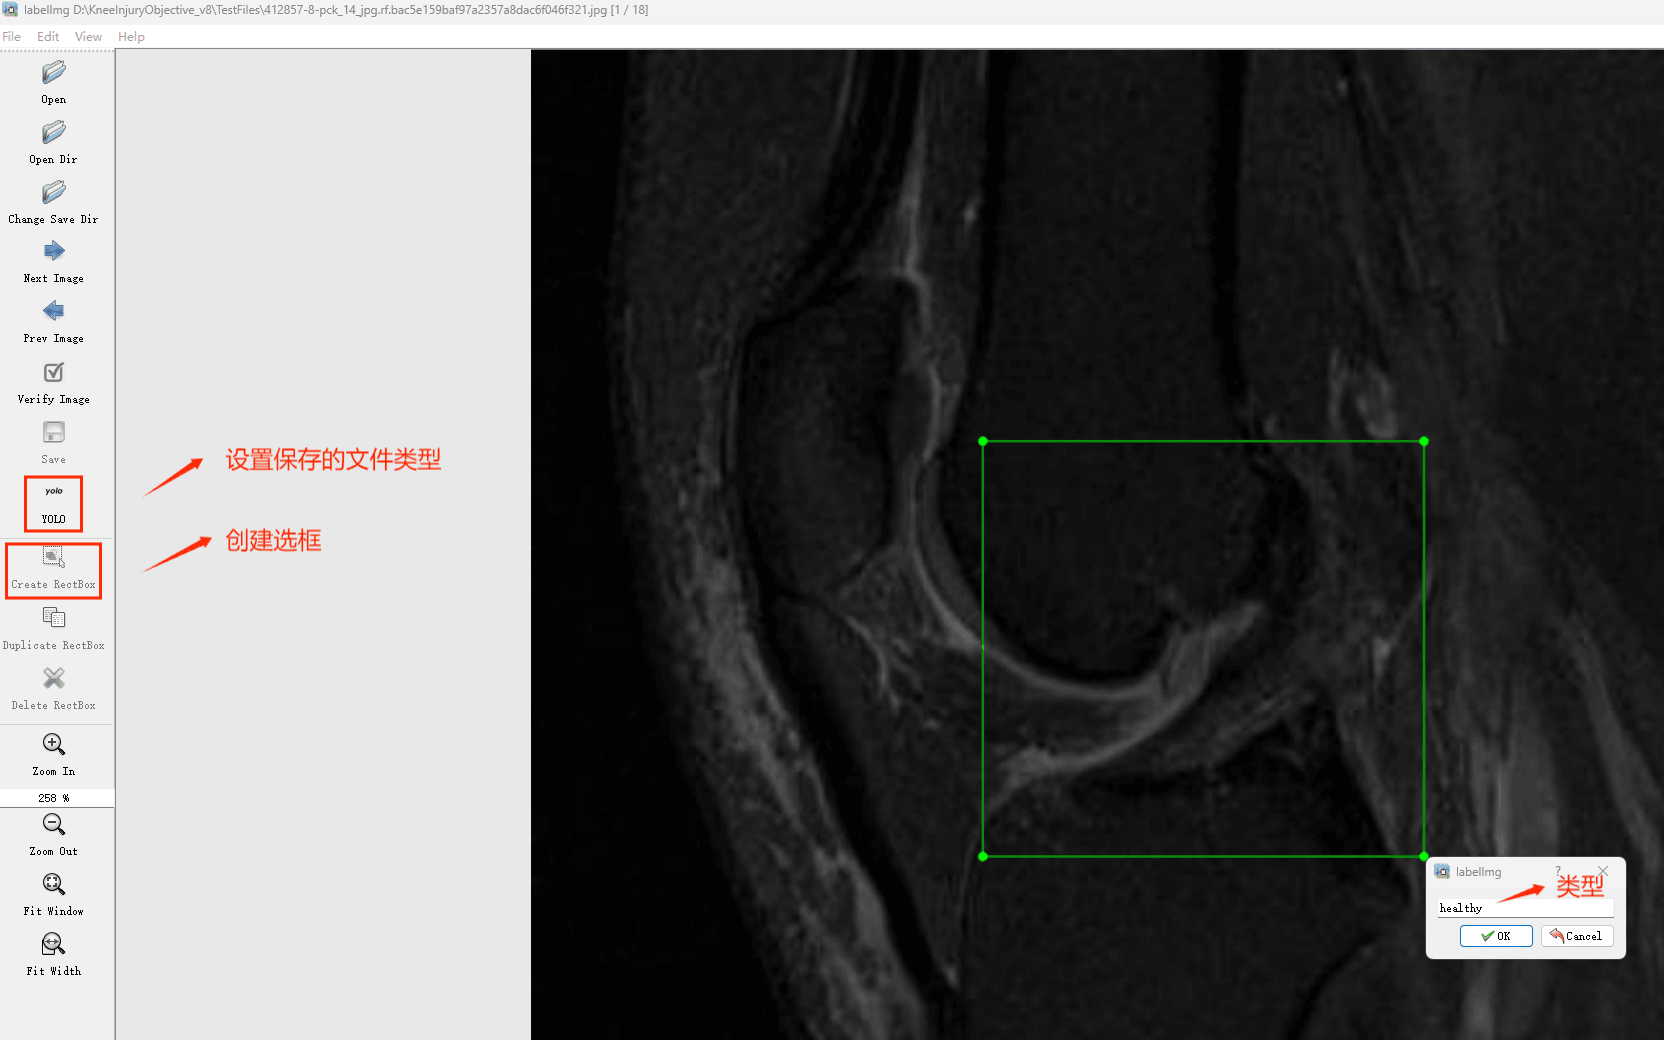

Tipps:通过搜集关于数据集为各种各样的膝关节损伤相关图像,并使用Labelimg标注工具对每张图片进行标注,分3检测类别,分别是’膝盖韧带断裂’, ‘膝盖完全健康’, ‘膝盖部分受伤’。

目标检测标注工具

(1)labelimg:开源的图像标注工具,标签可用于分类和目标检测,它是用python写的,并使用Qt作为其图形界面,简单好用(虽然是英文版的)。其注释以 PASCAL VOC格式保存为XML文件,这是ImageNet使用的格式。此外,它还支持 COCO数据集格式。

初识labelimg

打开后,我们自己设置一下

在View中勾选Auto Save mode

接下来我们打开需要标注的图片文件夹

并设置标注文件保存的目录(上图中的Change Save Dir)

接下来就开始标注,画框,标记目标的label,然后d切换到下一张继续标注,不断重复重复。